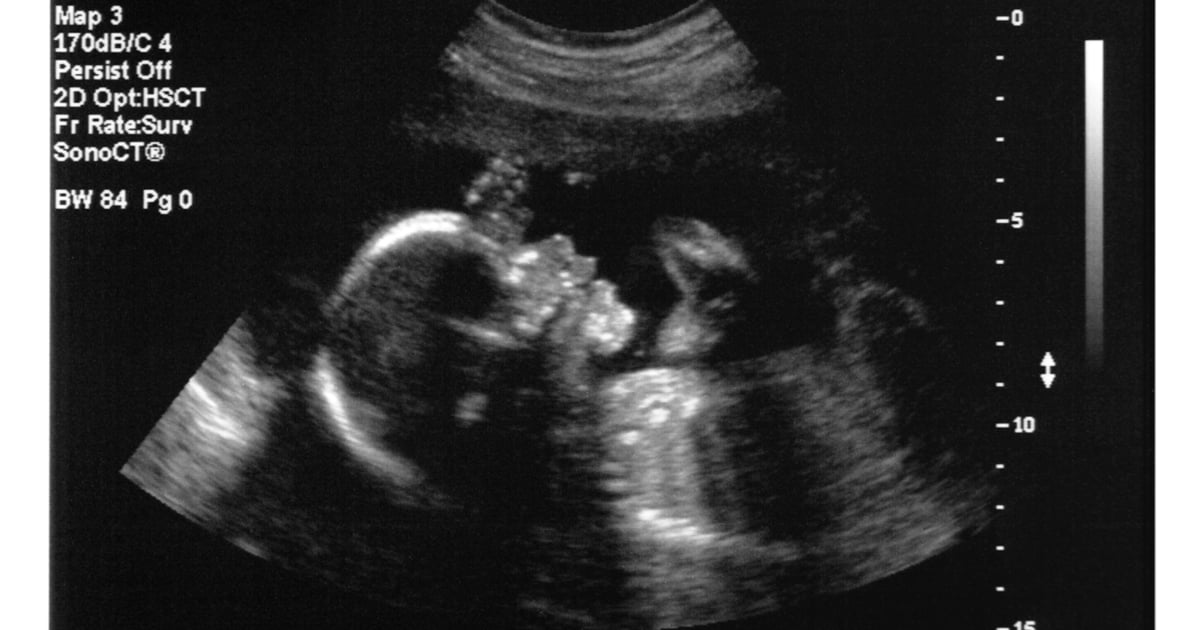

GE Ultrasound Gear Riddled With Bugs, Open to Ransomware & Data Theft

Thankfully, GE ultrasounds aren't Internet-facing. Exploiting most of the bugs to cause serious damage to patients would require physical device access.